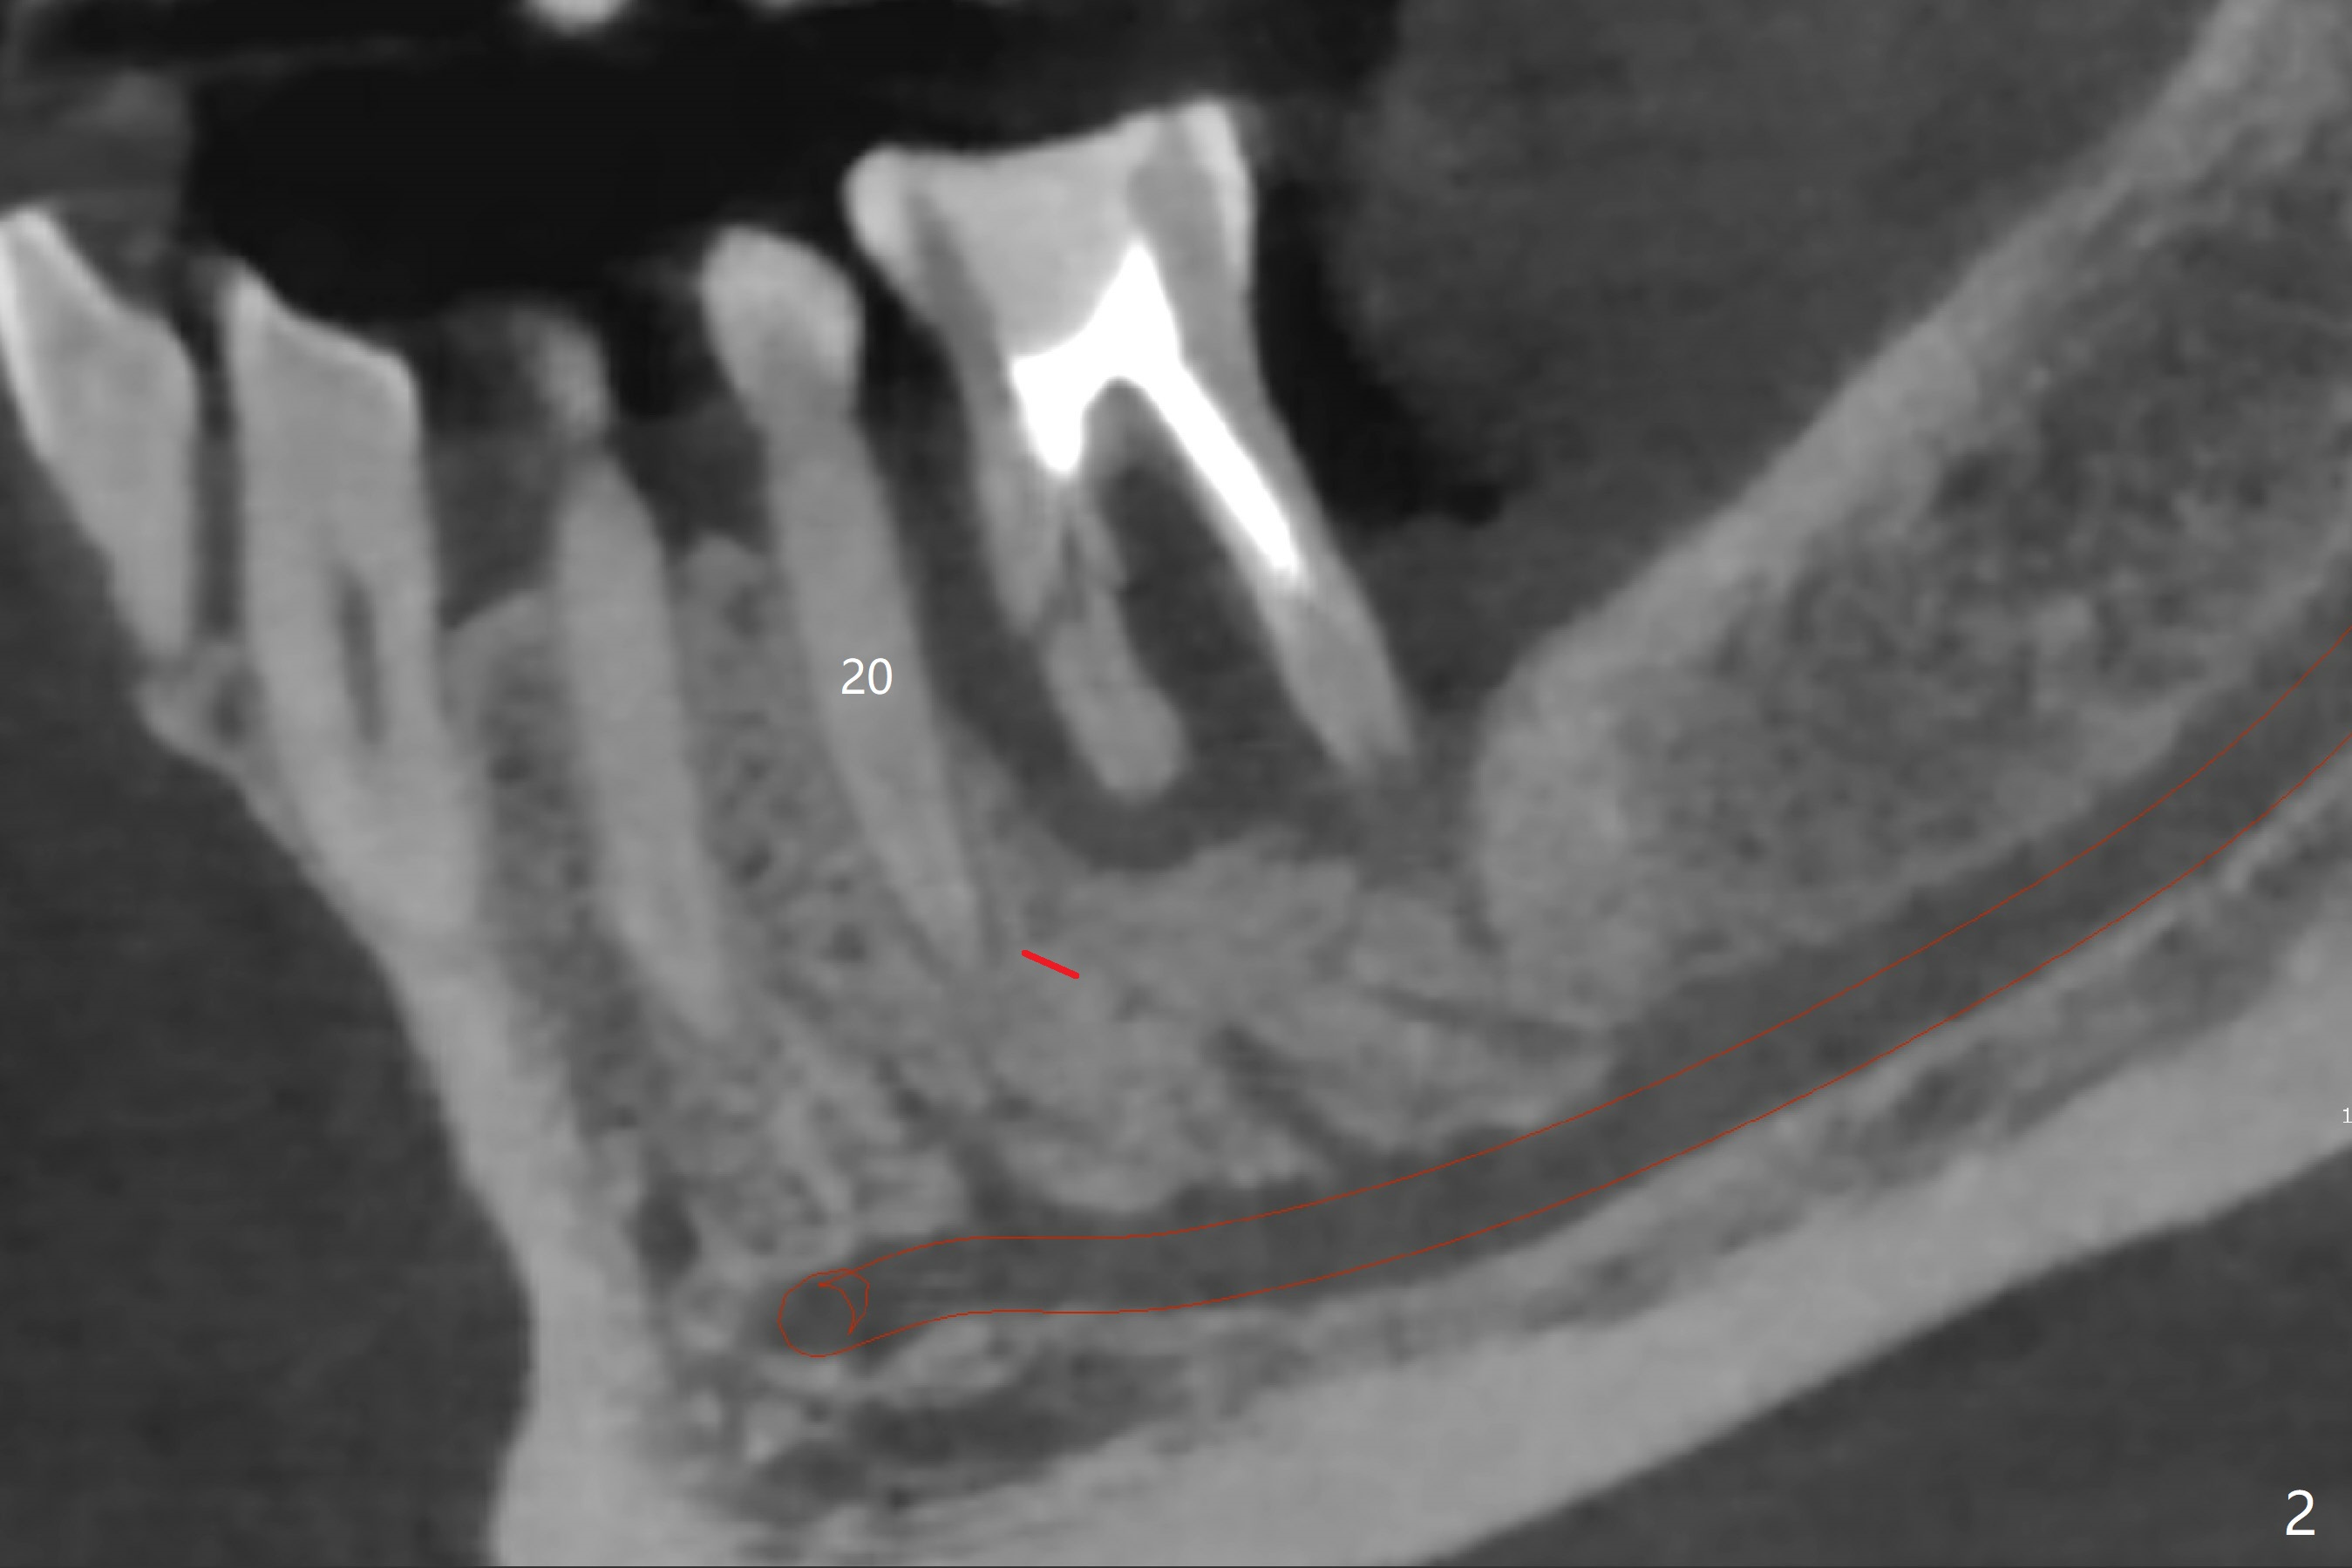

Placement M

When the patient finally agrees to have the tooth #19 to be extracted for implant (Fig.1), there is also mesial bone loss associated with mesial root fracture (Fig.2). To avoid truncation of the blood vessels toward the apex of the tooth #20 (Fig.2 black shadow and red line; Fig.4-6 (lab design) red symbols), a 5x10 mm implant will be placed more distal than the earlier design when the septum was present. The implant is also to be placed slightly higher than the native bone to improve crown/implant ratio; i.e., equical to the buccal, lingual and distal crests (Fig.3-6). Allograft will be placed in the gaps. After distal placement with minor axial change, new treatment plan is born. Return to Lower Molar Immediate Implant, Prevent Molar Periimplantitis (Protocols, Table), Trajectory, Weichat Xin Wei, DDS, PhD, MS 1st edition 01/14/2019, last revision 12/28/2019